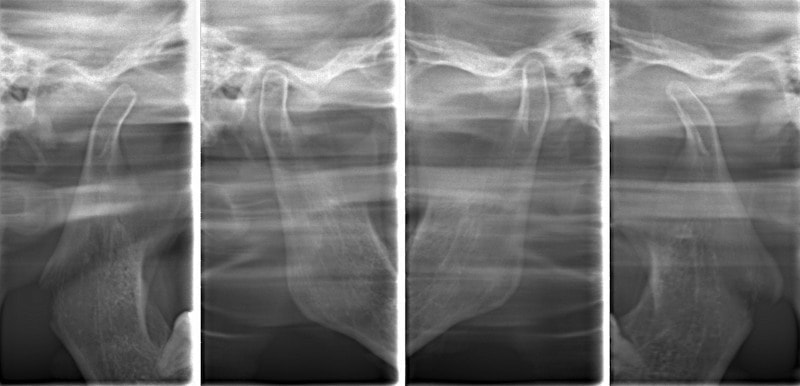

顎関節レントゲン分析

反対咬合の方はやはり下顎肢が細い傾向にあります。